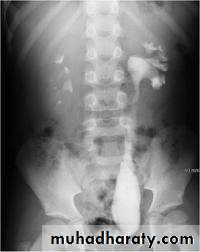

Renal agenesis :

- incidental finding.

- The opposite kidney shows compensatory hypertrophy.

- Can be diagnosed as absent kidney on ultrasound or CT.

- IVU will show a single kidney with active contrast excretion .